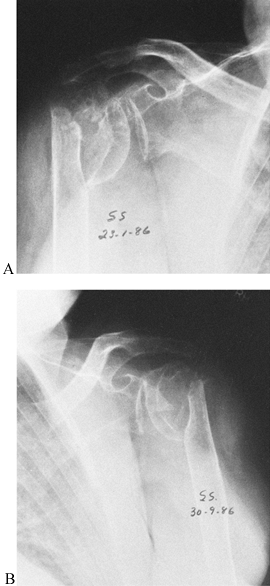

Figure 27.6.

Bilateral painless pseudarthrosis of the proximal humerus in a 72-year-old woman. This patient had adequate motion in her shoulders for her activities of daily living. |

individuals, who, if sedentary, may function reasonably well with a

painless pseudarthrosis or a malunion that does not interfere

significantly with their activities of daily living. Consequently,

premorbid patient activity, age, occupation, and hand dominance play

important roles in the decision whether to surgically repair a proximal

humerus nonunion (Fig. 27.6).